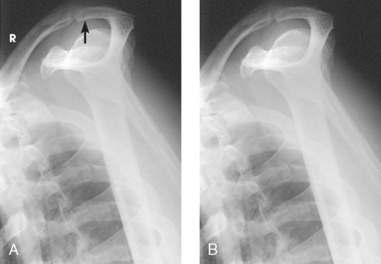

Fig. 5-14 A, AP shoulder, external rotation humerus: greater tubercle in profile (arrow). B, AP shoulder, neutral rotation humerus: greater tubercle (arrow).

Fig. 5-15 AP shoulder, internal rotation humerus: greater tubercle (arrow); lesser tubercle in profile (arrowhead).

External rotation: The greater tubercle of the humerus and the site of insertion of the supraspinatus tendon are visualized (see Fig. 5-14, A).

Neutral rotation: The posterior part of the supraspinatus insertion, which sometimes profiles small calcific deposits not otherwise visualized (see Fig. 5-14, B), is seen.

Internal rotation: The proximal humerus is seen in a true lateral position. When the arm can be abducted enough to clear the lesser tubercle of the head of the scapula, a profile image of the site of the insertion of the subscapular tendon is seen (see Fig. 5-15).